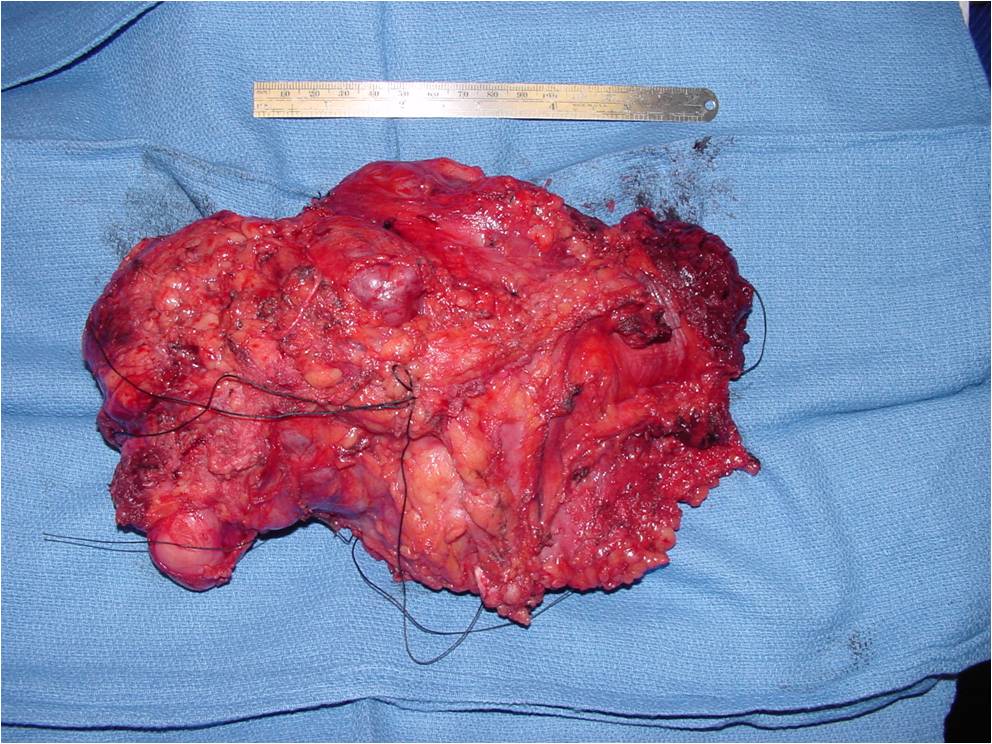

Gross Pathology

- Gross appearance is variable

- Ranging from soft to firm

- Gray to pink

- Occasionally have a faintly lobulated pattern

- Grossly obvious cartilage is rarely visualized

- Wide/Radical limb sparing surgery whenever feasible (most cases)

- Amputation for very large or unresectable tumors